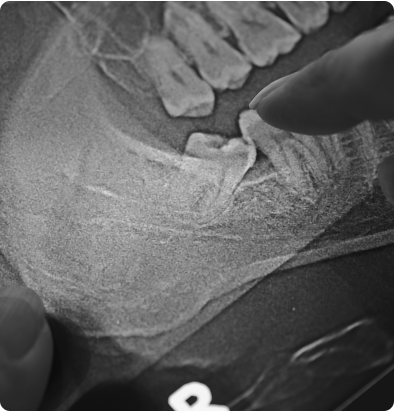

Lorsque les dents de sagesse sont incluses, partiellement sorties ou mal positionnées, leur extraction peut prévenir des complications : infections, douleurs, déplacements des autres dents.

Nous utilisons l’imagerie 3D pour planifier l’intervention et anticiper la structure osseuse et nerveuse. La chirurgie est réalisée sous anesthésie locale, dans un cadre sécurisé.